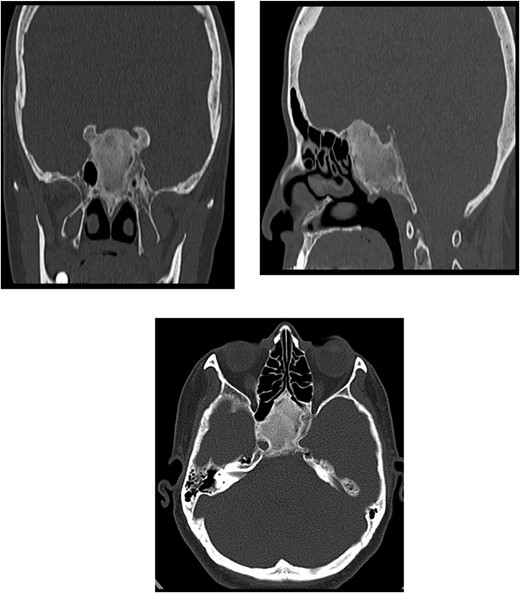

A 56-year-old female presented with a 1-year history of intermittent headaches, which had been increasing in severity and intensity over the last 2 months. The headache was mainly in the right parietal region, throbbing in nature and did not display diurnal variation. The severity of the headache was stated as 7–8 degrees on the Numerical Rating Pain Scale (NRPS; [6]). The pain was partially relieved with analgesia (acetominophen and ibuprofen). She also complained of mild right nasal congestion and intermittent mild otalgia. Physical examination was normal apart from nasal septal deviation. Computed tomography (CT) of the paranasal sinuses showed expansion of the sphenoid bone demonstrating diffuse ground-glass matrix and sclerosis obliterating the sphenoid sinus cavity (Fig. 1). Magnetic resonance imaging (MRI) was highly suggestive of fibrous dysplasia of the sphenoid bone, which appeared as expanded mass with dark T2 signal and T1 hypointense signal (Figs 2 and 3). Near-total excisional biopsy was performed using endoscopic transeptal approach to sphenoid sinuses. Histopathological examination of several pieces of greyish tan and brown bony tissue measuring 3.5 × 2.5 × 1.7 cm. showed branching irregular trabeculae of woven bone with intervening hypocellular fibrous stroma, consistent with a diagnosis of FD (Fig. 4). The patient’s headaches improved greatly following surgery. Two years post-op she reports infrequent headache with a severity of 2 on NRPS.

CT of the paranasal sinuses showing expansion of the sphenoid bone demonstrating diffuse ground-glass matrix and sclerosis obliterating the sphenoid sinus cavity.